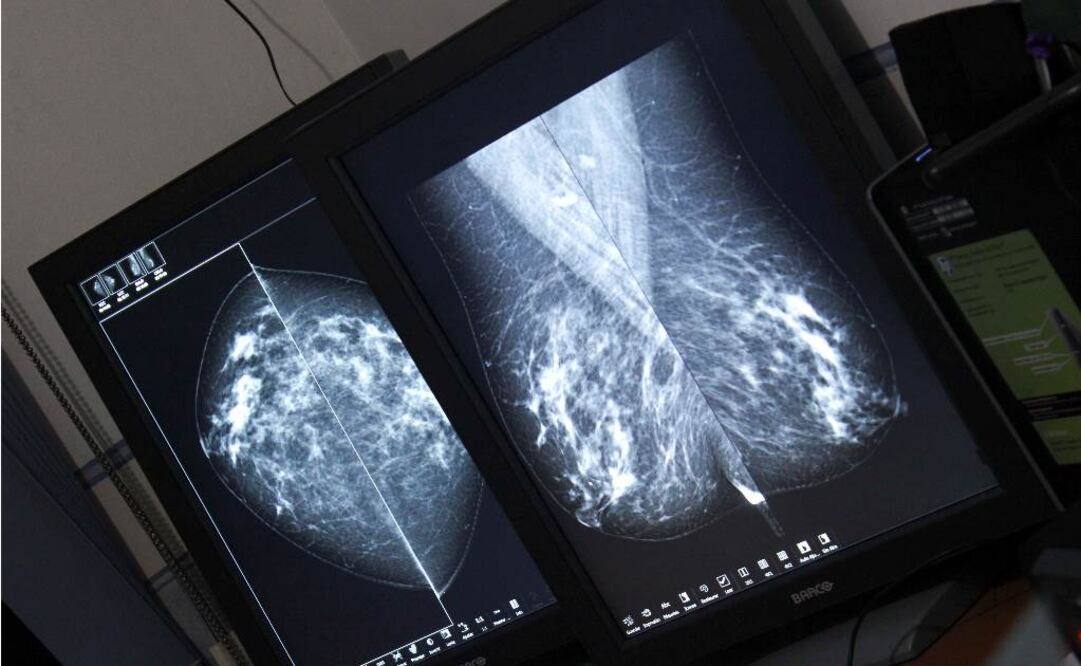

En el Distrito Federal se han aplicado más de un millón de mastografías desde 2007, informó el secretario de Salud capitalino, Armando Ahued.

Sin embargo, comentó que 70% de los diagnósticos se realizan en etapas avanzadas, por lo que pidió a las mujeres practicarse la prueba a tiempo.

Explicó 65% de las muertes por este mal pueden evitarse con la detección temprana.

Se cuenta con 35 mastógrafos y 19 más subrogados; también con un Centro de Diagnóstico Radiológico para el Cáncer de Mama, con trasmisión de imágenes digitales vía internet, así como equipos de ultrasonido para el diagnóstico de mama y una mesa de estereotaxia para la toma de biopsias, con el fin de realizar la detección oportuna del cáncer a mujeres mayores de 40 años de edad.